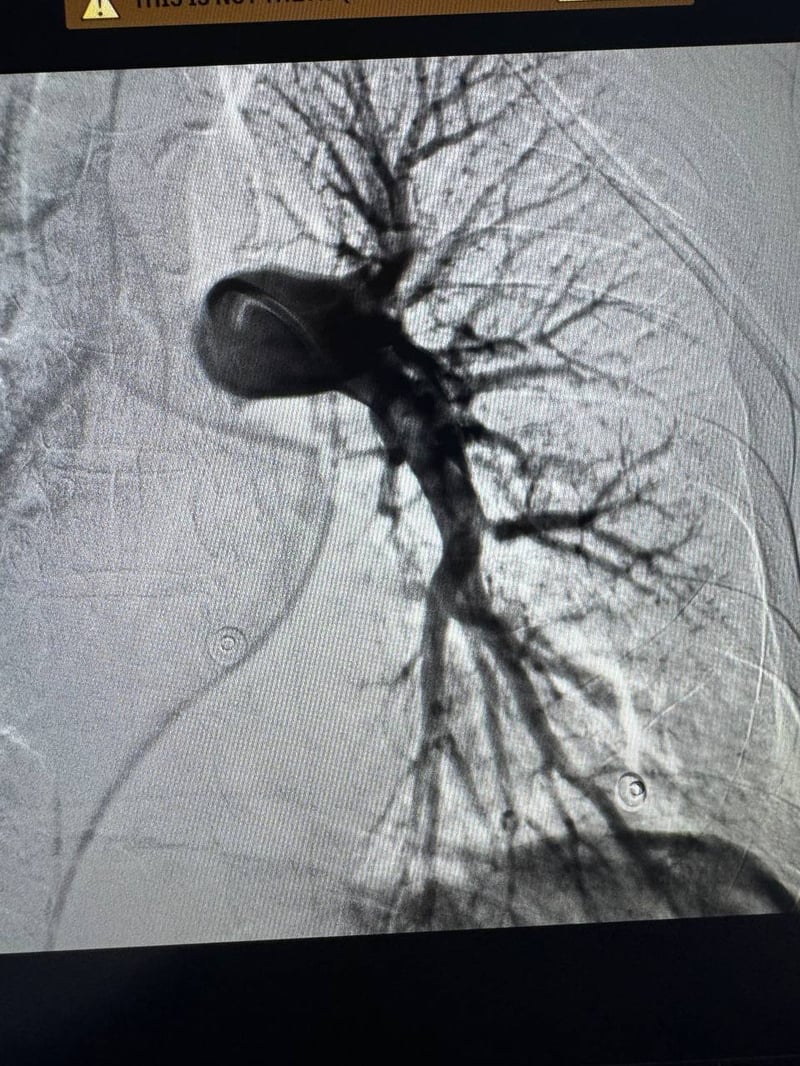

Пан Тарас звернувся до лікаря через сильну задишку після активних занять спортом. Обстеження виявило масивне скупчення тромбів у легеневій артерії, що могло спричинити раптову смерть. Чоловіка терміново доставили до Лікарні Святого Пантелеймона, де підтвердили діагноз — тромбоемболія легеневої артерії (ТЕЛА).

Інтервенційні кардіологи та анестезіологи виконали ендоваскулярну тромбаспірацію – малоінвазивне втручання, під час якого катетером дісталися до тромбів та видалили їх спеціальною аспіраційною системою. Пацієнт був при тямі й міг спілкуватися з лікарями.

На п’яту добу після втручання чоловіка виписали додому без скарг. Також уже планують його повернення до активного життя та спорту. Цим методом у лікарні врятували ще й другого пацієнта – військового з масивною тромбоемболією після мінно-вибухової травми.